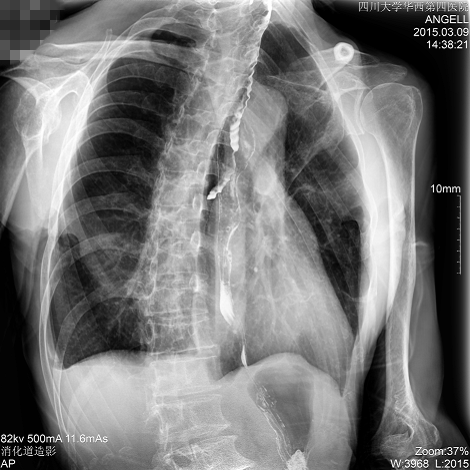

如下圖所示:該患者因吞咽時感到很難受,進食時也經常咳嗽故就醫診斷。使用多功能dr為病人進行消化道造影診斷,要求他吞鋇后發現,食道各段通過順利,形態規則,雙側梨狀窩不對稱左側稍淺,多次吞咽動作后,仍見鋇劑滯留,并見鋇劑進入氣管,屬于會厭征陽性。會厭功能紊亂,鋇劑進入了氣管。

圖為正位:通過動態影像可以清楚看到鋇劑進入了支氣管道且雙側梨狀窩不對稱

通過多功能dr可以診斷該病人的癥狀為會厭功能紊亂,鋇劑進入到了氣管。而在動態透視下可以清晰的觀察到鋇劑從何處進入氣管,可清晰顯示食管粘膜結構。使用多功能dr其獨特的視頻采集技術,可實時保存視頻并能實現900萬像素實時點片,才能獲取這樣清晰的病灶點。而常規dr只能拍攝靜態片,且成像效果大打折扣,因此較難確診病灶。